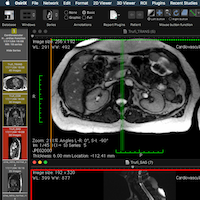

Faster GUI

Faster GUI